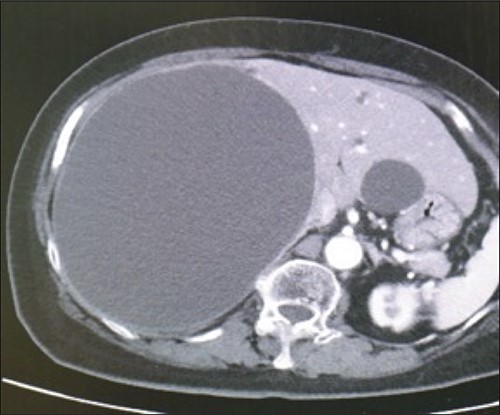

A 78-year-old female patient was followed up by a family doctor who pointed out a giant liver cyst (maximum diameter 11.5 cm) by abdominal echo 7 years ago. Her liver cyst was gradually increasing (maximum diameter 17 cm; Fig. 1), and she was at risk of cyst rupture, so she was referred to our hospital for surgical purposes. The laboratory data revealed no specific findings.

Preoperative computed-tomography imaging demonstrating giant liver cyst (axial section).